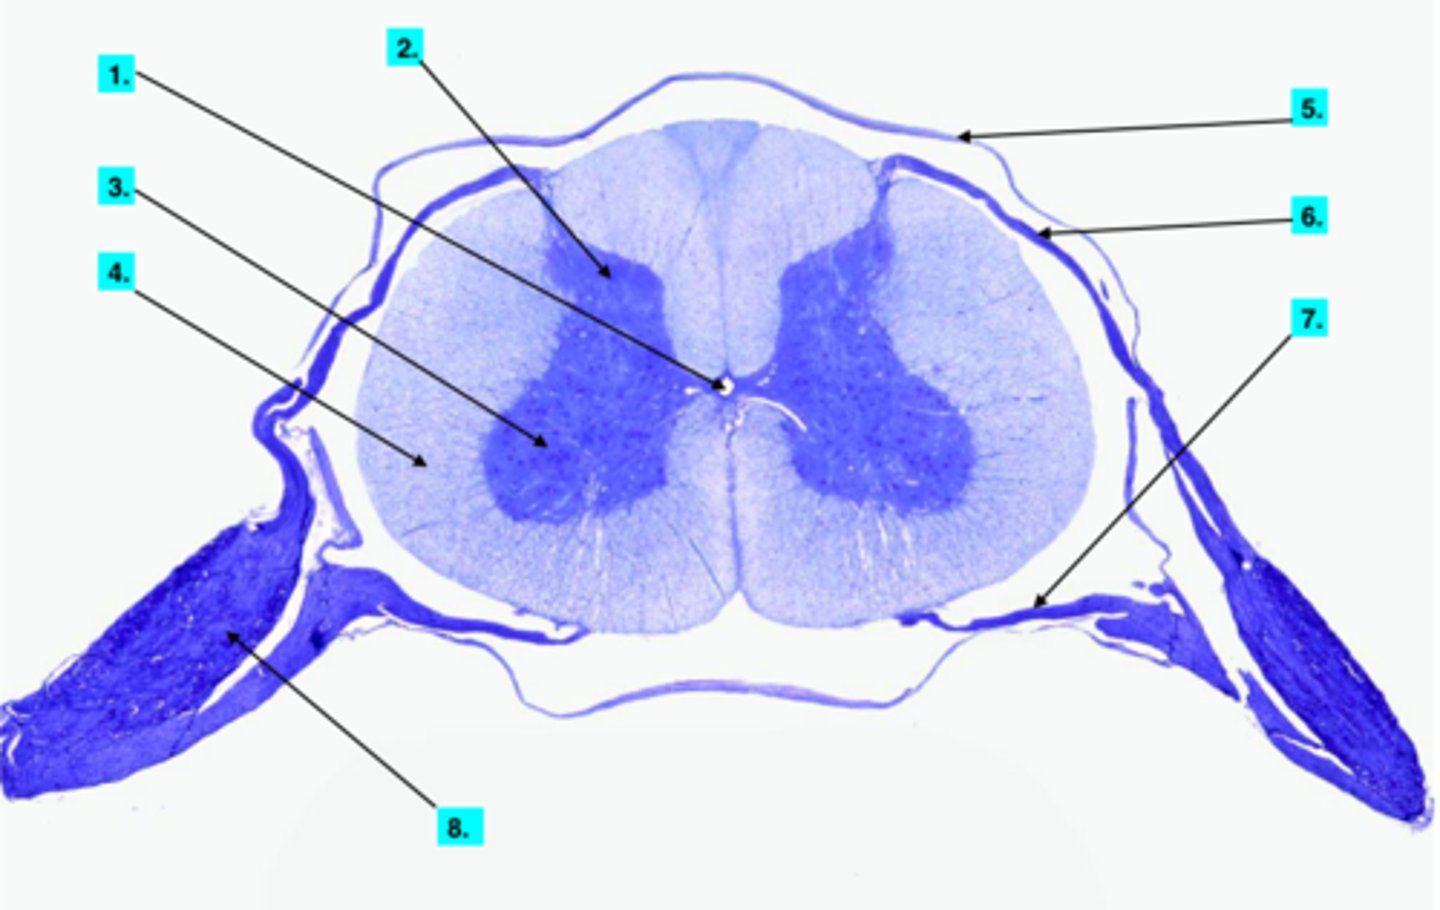

Anterior Gray Horn

Posterior Gray Horn (microscope slide spinal cord)

Anterior White Column

Posterior White Column (microscope slide spinal cord)

Ventral Root

7

Motor Neurons (microscope slide spinal cord)

What neurons are found here?

Dorsal Root

6

Dorsal Root Ganglion

8

Unipolar Neurons

What neurons are found in 8?

Pia Mater

Central Canal

Dura Mater

5

Anterior Median Fissure

Posterior Median Sulcus